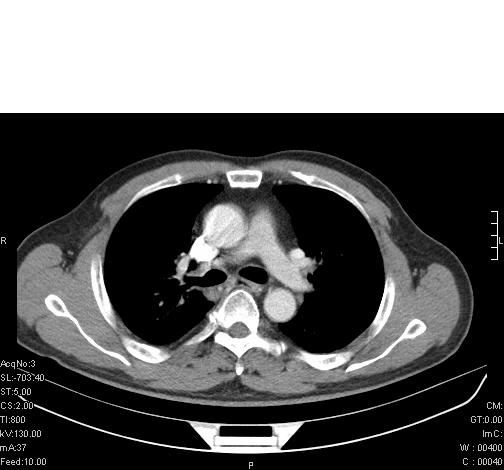

标题: CT6685:右肺阻塞性炎症,增强CT。

前几天,发了患者的平扫片,患者抗炎一周后增强扫描。右中叶病灶吸收明显,但下叶病灶未见明显吸收。右肺门可见结节影,看来凶多吉少

右肺下叶支气管管腔狭窄,管壁增厚,右下肺见斑片状高密度影,考虑右侧肺门中心肺癌伴阻塞性肺炎

右肺下叶散在的斑片状致密影,下叶支气管变窄。考虑:右肺慢性炎症。

右肺下叶支气管壁明显增厚,考虑癌症并阻塞性炎症、肺门淋巴结肿大

考虑右肺癌并阻塞性炎症、肺门淋巴结肿大

还是考虑右肺中央型肺癌可能性大

右肺下叶支气管壁不规则增厚,右肺下叶有斑片状影分布。考虑右肺中央型肺癌伴右肺下叶阻塞性改变。建议支纤镜检查。平扫比增强较好显示了病变情况。

右主支气管狭窄,管壁增厚。考虑右中心性肺ca伴阻塞性肺炎。